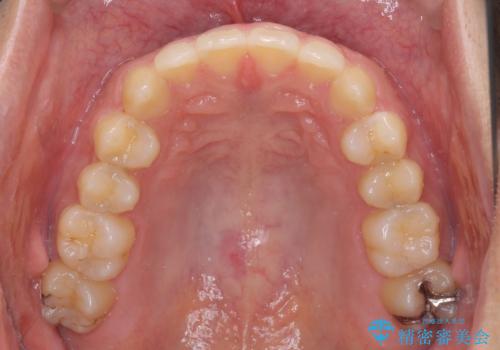

前歯の咬み合わせとデコボコを解消 インビザラインによる矯正治療

- 上下前歯のデコボコと深い咬み合わせを気にして来院された患者様です。

インビザラインによる上下歯列の拡大と、IPR(歯と歯の間を削る)にるスペースの獲得により、前歯のデコボコとディープバイトを改善することとしました。

もう少し下の前歯を整えたかったのですが、患者様の治療を早く終了させたいという希望により、細かい叢生を残しての終了となりました。